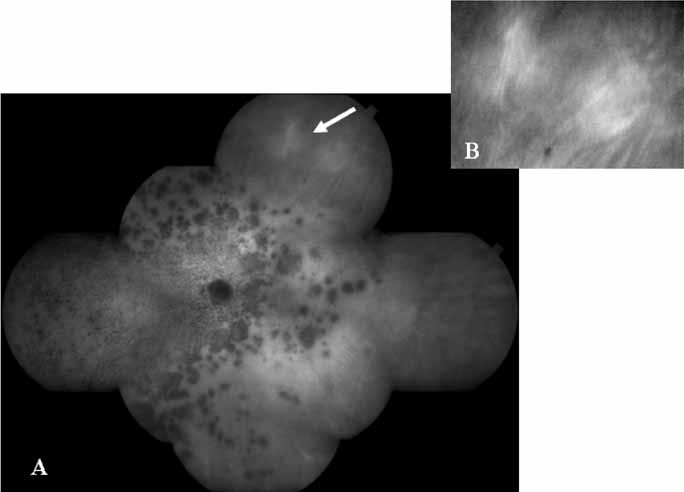

In a landmark article, Yannuzzi and associates18 demonstrated that ICG videoangiography was extremely useful in identifying well-demarcated localized areas of neovascularization in what had been classified as occult CNV by standard fluorescein angiography.19–24 In this study, 39% of 129 patients with “occult CNV” originally diagnosed as determined by fluorescein angiography were given a revised diagnosis of “well-defined neovascular lesions” based on the information obtained from the ICG study (Fig. 1). One study revealed that approximately 40% of patients with occult CNV diagnosed actually presented with early, well-defined focal areas of fluorescence on ICG videoangiography.25 They further defined two potential subgroups of occult CNV: those with and those without serous pigment epithelial detachments (PEDs) accompanying the occult neovascular process. They also pointed out that ICG angiography offered a potential advantage in identifying neovascular lesions when there was clinical evidence of recurrent CNV after previous laser photocoagulation treatment.

Subsequently, Yannuzzi and colleagues25 and Guyer and associates26 evaluated the usefulness of ICG angiography in identifying localized areas of CNV in patients with occult CNV with or without a serous PED. In a careful evaluation of more than 680 patients, they identified 22% of patients with localized lesions that might be amenable to laser therapy—lesions that would otherwise be classified as untreatable based on guidelines for laser photocoagulation (Figs. 2 and 3). As a result of this improved imaging technique, as many as two to three times the number of patients would have been potentially eligible for laser treatment than would have been treatable based on fluorescein angiography alone.